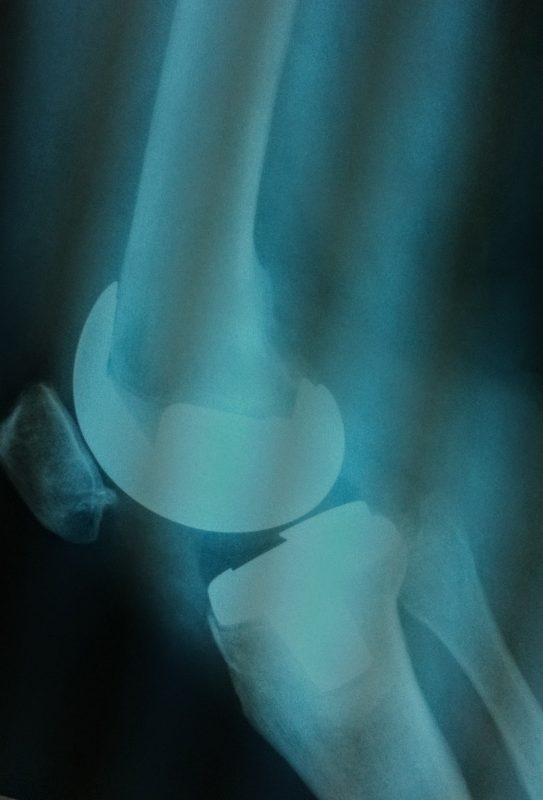

Σε αυτό το σημείο η Αρθροπλαστική Γονάτου αποτελεί μονόδρομο.